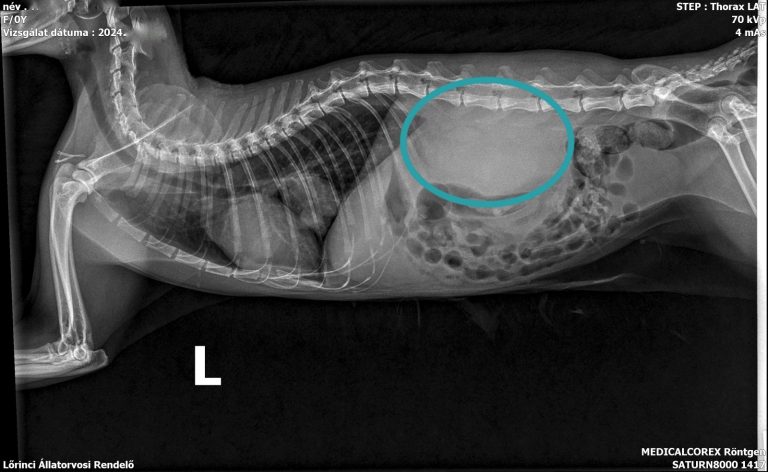

A képalkotó vizsgálatok közül a vesék (és a többi hasüregi szerv) vizualizálásához a hasi ultrahangot alkalmazzuk a leggyakrabban, de a megnagyobbodott vese kontúrja a röntgenfelvételeken is ábrázolódhat.

Megnagyobbodott vese röntgen felvétele macskában

A vesék mellett a betegség érintheti a tápcsatornát, illetve a hasi nyirokcsomók is megnagyobbodhatnak. Végleges és biztos diagnózishoz vékonytű aspiráció vagy biopsziás mintavétel szükséges.